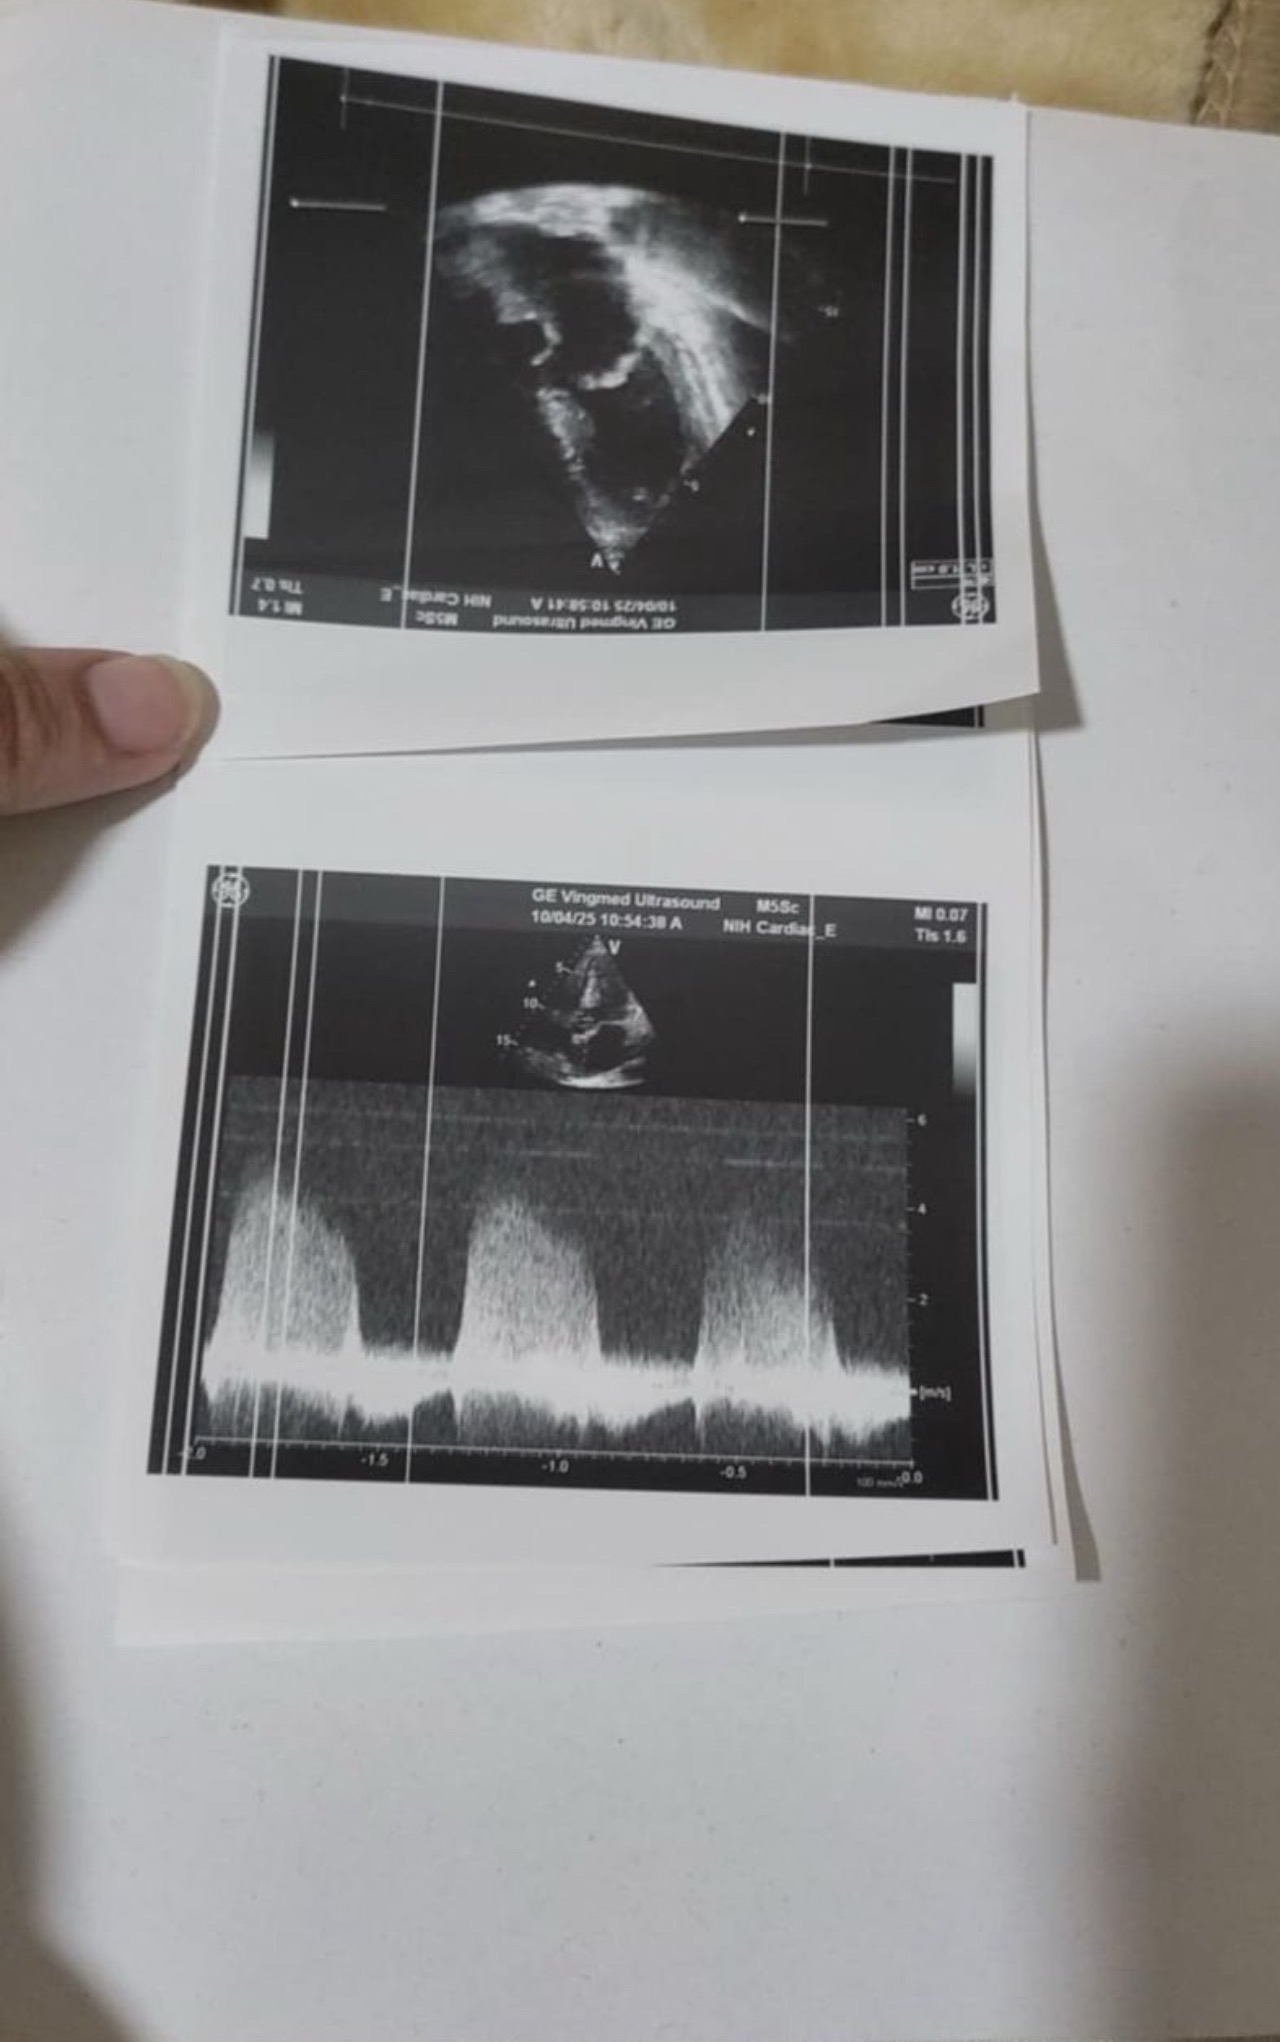

alse My father’s health is another major concern. He loses consciousness from time to time and urgently needs heart surgery. But in Gaza, there are no hospitals equipped to perform such a surgery. There is a severe shortage of medicine, and adequate medical treatment is hard to come by. The basic necessities, such as clean water and fresh air, are also scarce. Watching my father suffer, knowing that he needs medical attention that we cannot provide, is one of the hardest things I have ever had to endure.